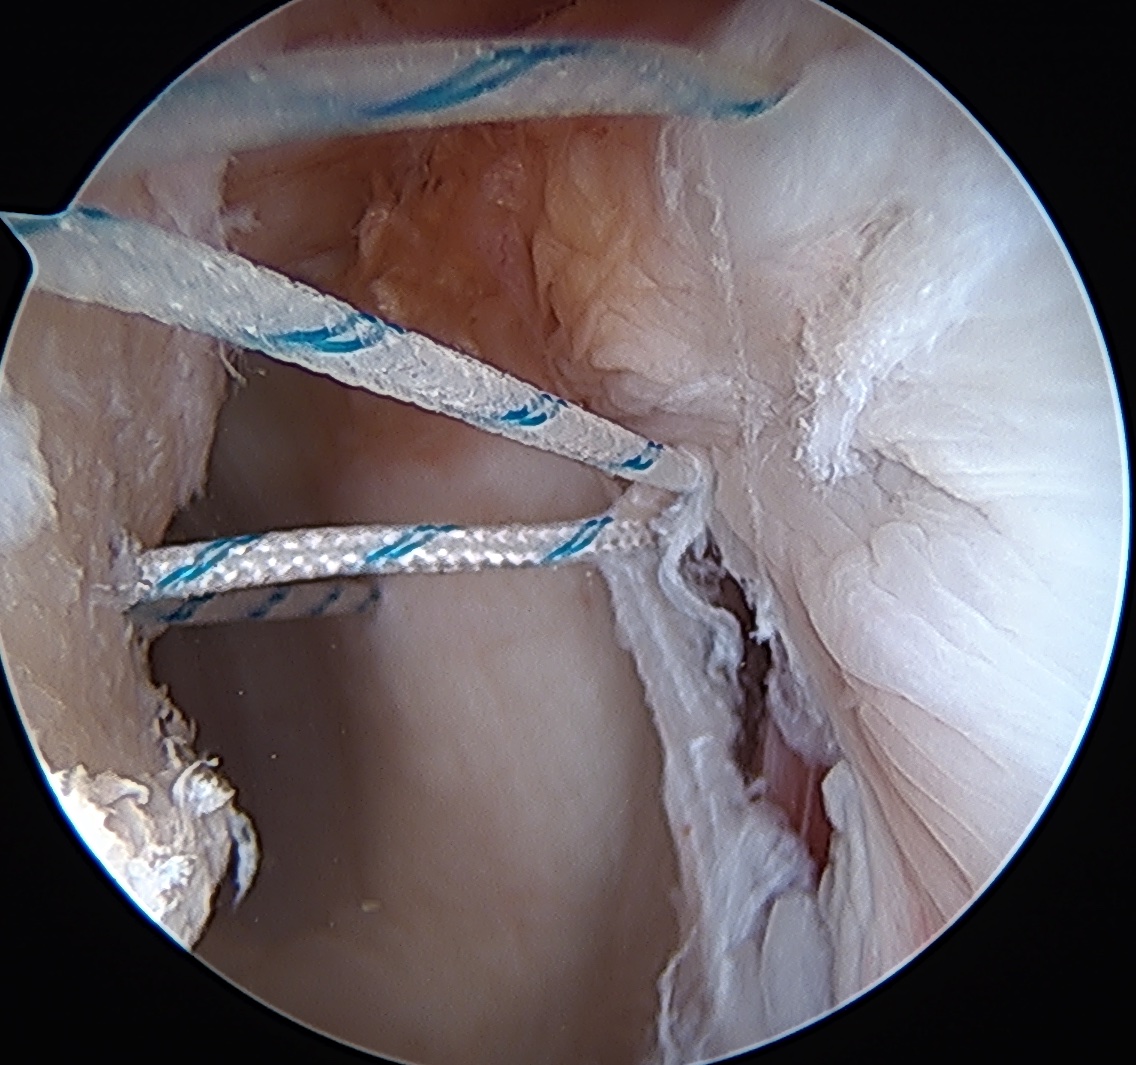

Technique

- view from anterior portal

- posterior cannula over Hill Sachs lesion

- debride base of Hill Sachs to bleeding bone

- insert anchors at medial aspect of defect

- suture passer / birds beak to take bite of capsule

- tie down into defect

- can tie blind or put camera into subacromial space

Anchor insertion into Hill Sachs lesion